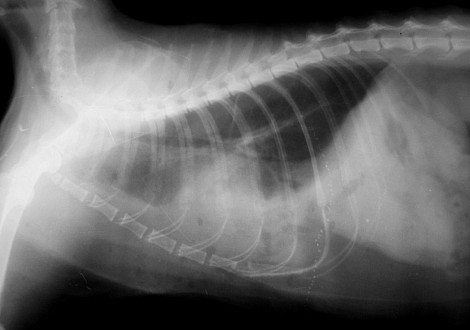

2. рентгенография грудной клетки – данный вид исследования позволяет определить наличие плеврального выпота, пневмоторакса, гидроторакса.

Пневмоторакс – это скопление свободного воздуха в плевральной полости.

Дренажную трубку удаляют при восстановлении дыхания, рентгенографическом подтверждении расправления легких, достижении объема дренируемой жидкости менее 5 мл/кг/сутки, а также при отсутствии утечки воздуха в дренажной системе.

Удаляют дренаж под местной анестезией и накладывают тугую повязку. В течение следующих суток животное остается под тщательным наблюдением ветеринарных врачей для мониторинга признаков рецидива. На следующий день после снятия дренажа проводится контрольное рентгенографическое исследование. При положительной динамике животное на поддерживающей терапии выписывают домой с назначением контрольных наблюдений и диагностических мероприятий.